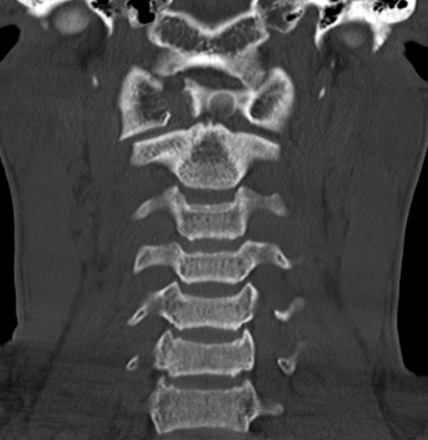

C1, Do One, Teach One

A 16-year-old high school football player presented to the ER after being tackled and contacting helmet-to-ground. He was diagnosed with a concussion by a sideline physician . The patient noted dizziness, foggy thinking, and neck stiffness that he had difficulty localizing, but he and parents felt his symptoms were improving. He remained on the sideline and was ambulatory until the conclusion of the game, but as he cooled down his neck became stiff and painful, prompting ER evaluation. Patient denied any radiating symptoms or loss of consciousness. Physical exam was remarkable for pain at terminal flexion and extension, glazed over appearance, but strength and sensation intact.

Read More...